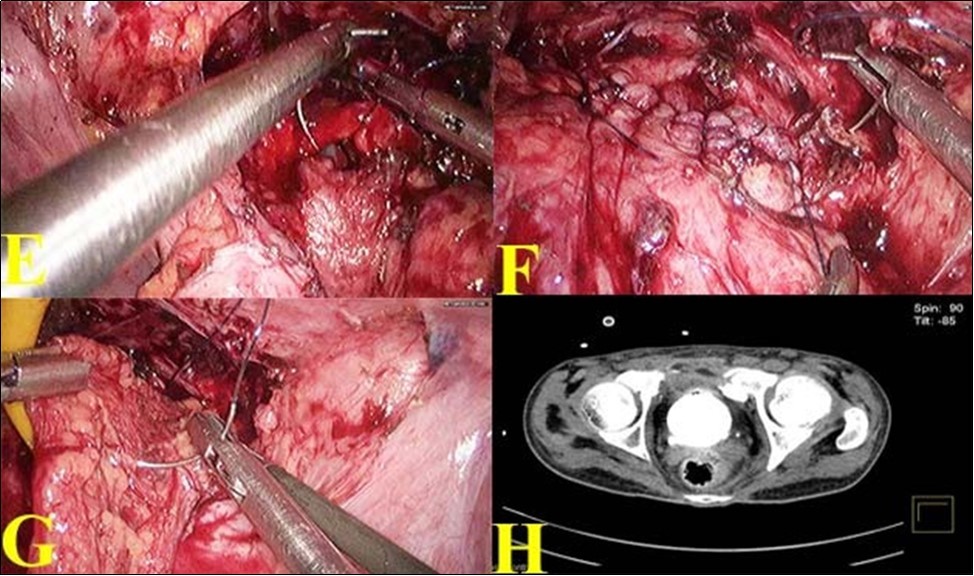

(Figure 2 (G). SPC was reinserted. Bladder was again distended with dilute methylene blue solution to make sure that the closure was watertight. A tube drain was placed. Postoperatively patient made an uneventful recovery. Tube drain was removed on 7thpostoperative day when the drainage was less than 10ml. SPC was removed on the 10thpostoperative day. CT cystogram was done on 21st day which showed no extravasation Figure 2 (H). Patient voided freely on removal of urethral catheter on 21st day.

Figure 2.E. Bladder rent closing with barbed suture ; F. Suturing completed; G. Omental reinforcement over the suture line; H. Post operative CT showing healed bladder.